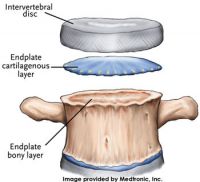

An intervertebral disc is a strong ligament that connects one vertebral bone to the next. The discs are the shock-absorbing cushions between each vertebra of the spine. Each disc has a strong outer ring of fibers, called the annulus fibrosus, and a soft, jelly-like center, called the nucleus pulposus. The annulus is the strongest area of the disc and the ligament that connects each vertebra together. The nucleus, or center of the disc, is hydrated and serves as the main shock absorber. Discs in the spine increase in size from the neck to the low back as there are increasing needs for shock absorption due to weight and gravity. These specific disc ligaments function just like knee ligaments and shoulder ligaments do. They allow the spine to move so we can bend forward, backward and sideways. Just like other ligaments, the discs can be injured.

An intervertebral disc is a strong ligament that connects one vertebral bone to the next. The discs are the shock-absorbing cushions between each vertebra of the spine. Each disc has a strong outer ring of fibers, called the annulus fibrosus, and a soft, jelly-like center, called the nucleus pulposus. The annulus is the strongest area of the disc and the ligament that connects each vertebra together. The nucleus, or center of the disc, is hydrated and serves as the main shock absorber. Discs in the spine increase in size from the neck to the low back as there are increasing needs for shock absorption due to weight and gravity. These specific disc ligaments function just like knee ligaments and shoulder ligaments do. They allow the spine to move so we can bend forward, backward and sideways. Just like other ligaments, the discs can be injured.